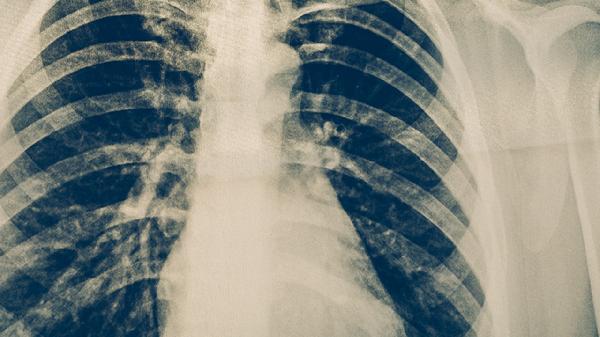

肺结核患者适合适量食用苹果、梨、香蕉、猕猴桃、橙子等水果,有助于补充营养并促进康复。肺结核是由结核分枝杆菌引起的慢性传染病,患者需在医生指导下规范用药,同时通过饮食调理增强免疫力。